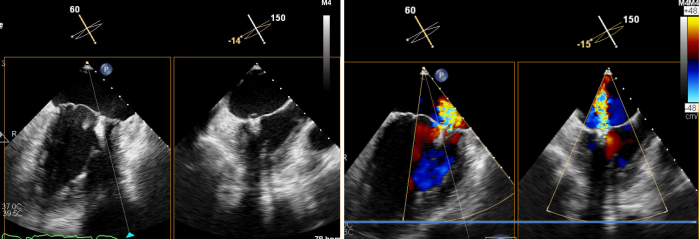

术后心脏彩超所示:二尖瓣无返流

术后,患者二尖瓣返流情况得到了明显改善,其他各项生理指标也均正常,术后第二天即可下床活动,呼吸困难和乏力症状显著缓解,心脏负荷明显减轻。术后心脏彩超结果显示,其左室射血分数上升到62%,生活质量获得极大提升。